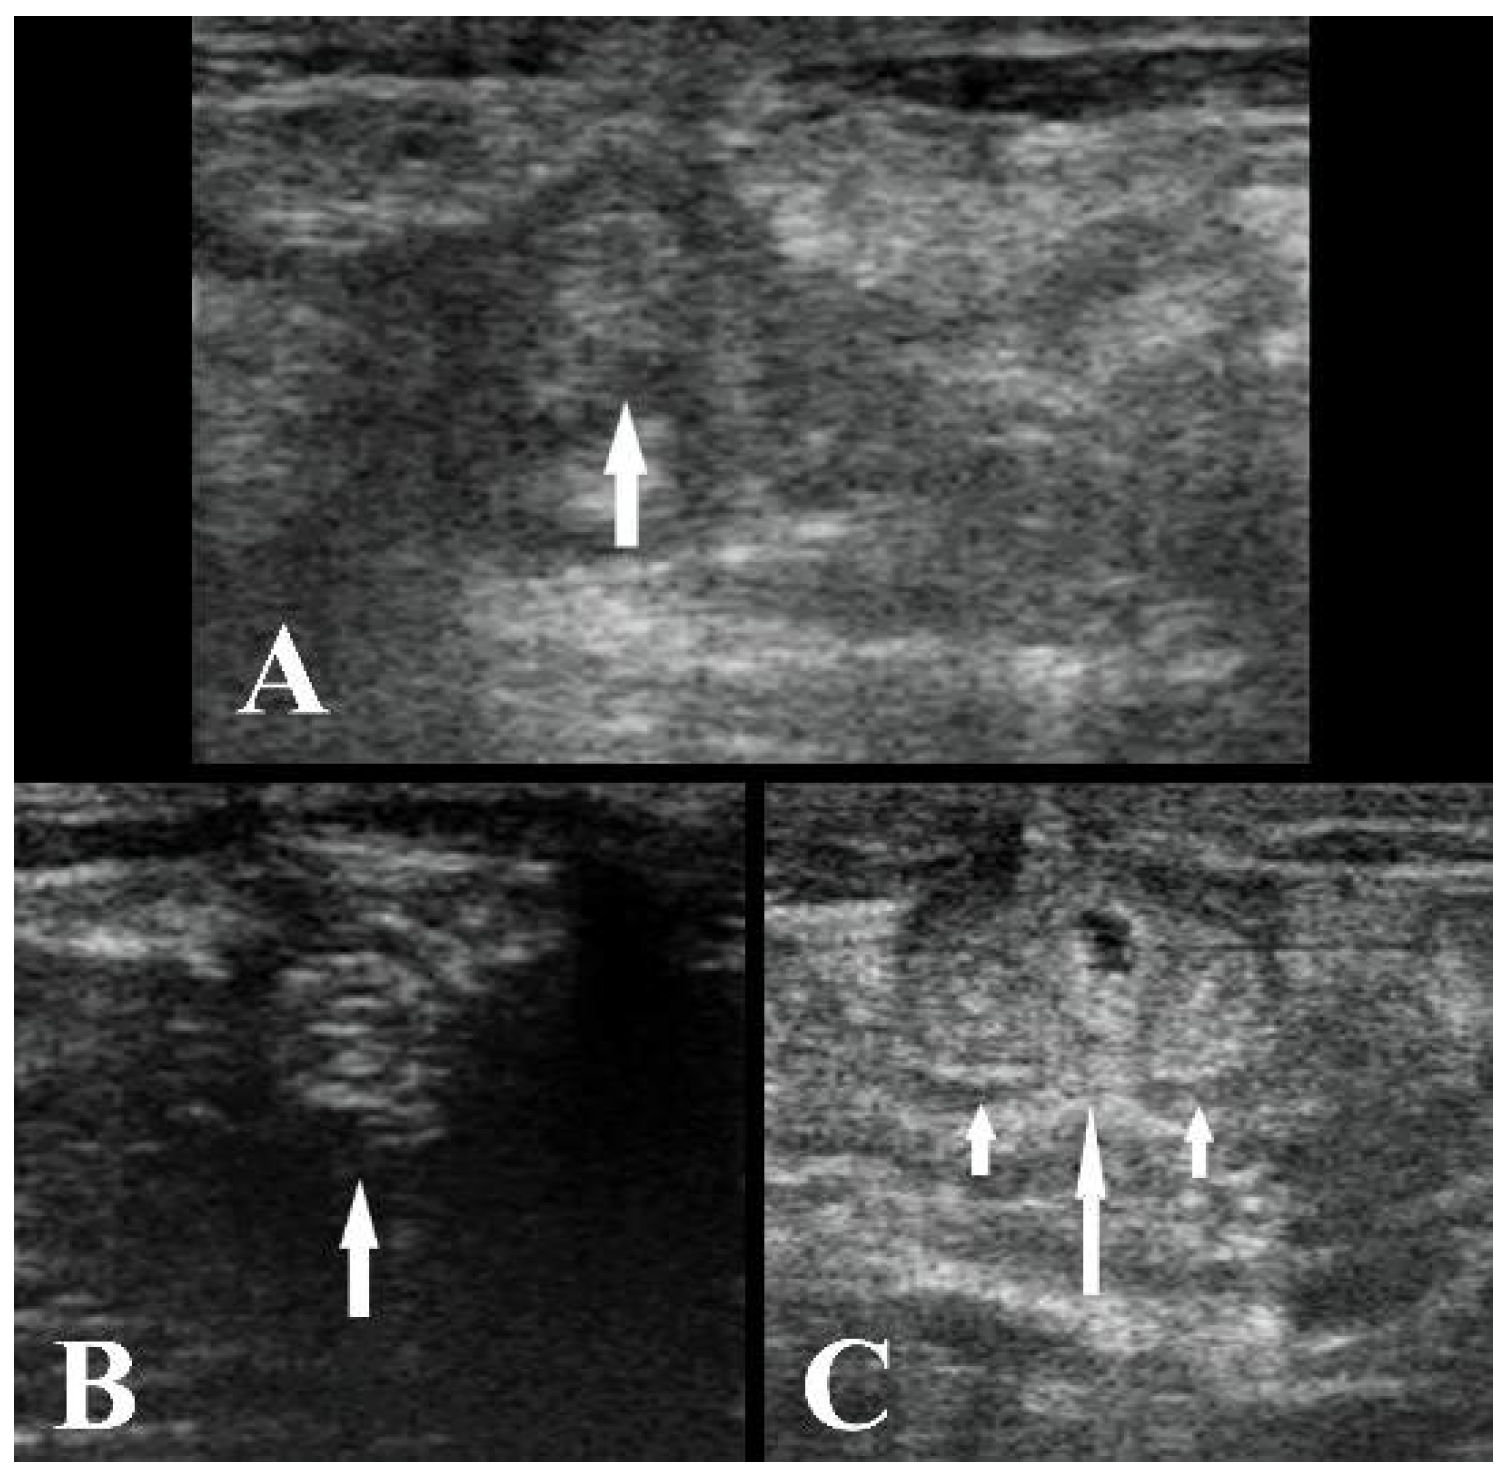

2.2. Ultrasonography Technique

3. Results